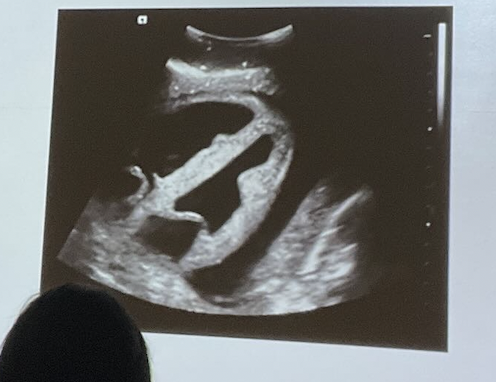

Que Evalua E-FAST en pleura

Hemidiafragmas y pleura para detectar neumotórax y hemotórax